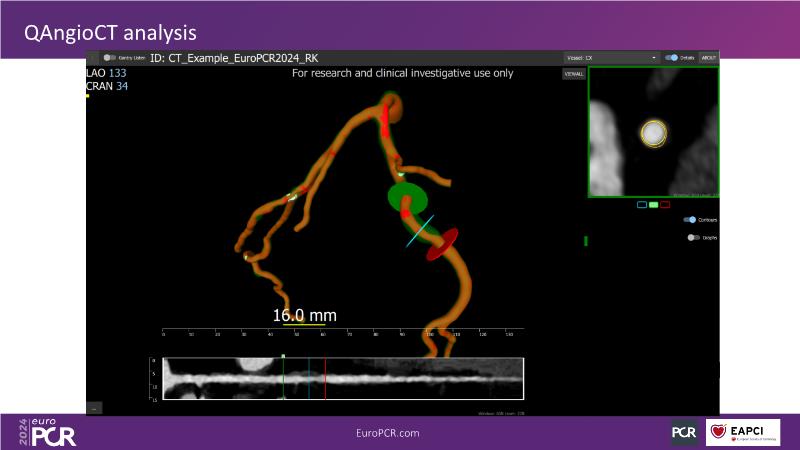

QFR: the next-generation diagnostic tool for epicardial and microvascular disease in the cathlab

Join this session to delve into the cutting-edge capabilities of the newest QFR technology, allowing for rapid coronary vessel analysis in under 30 seconds. Gain insight into the diagnostic potential of QFR-IMR for assessing coronary microvascular dysfunction and understand its implications for patient care. Explore the transformative impact of QFR on treatment planning, paving the way for innovative approaches to managing coronary artery disease.

- To learn how QFR paves the way for new horizons in treatment planning